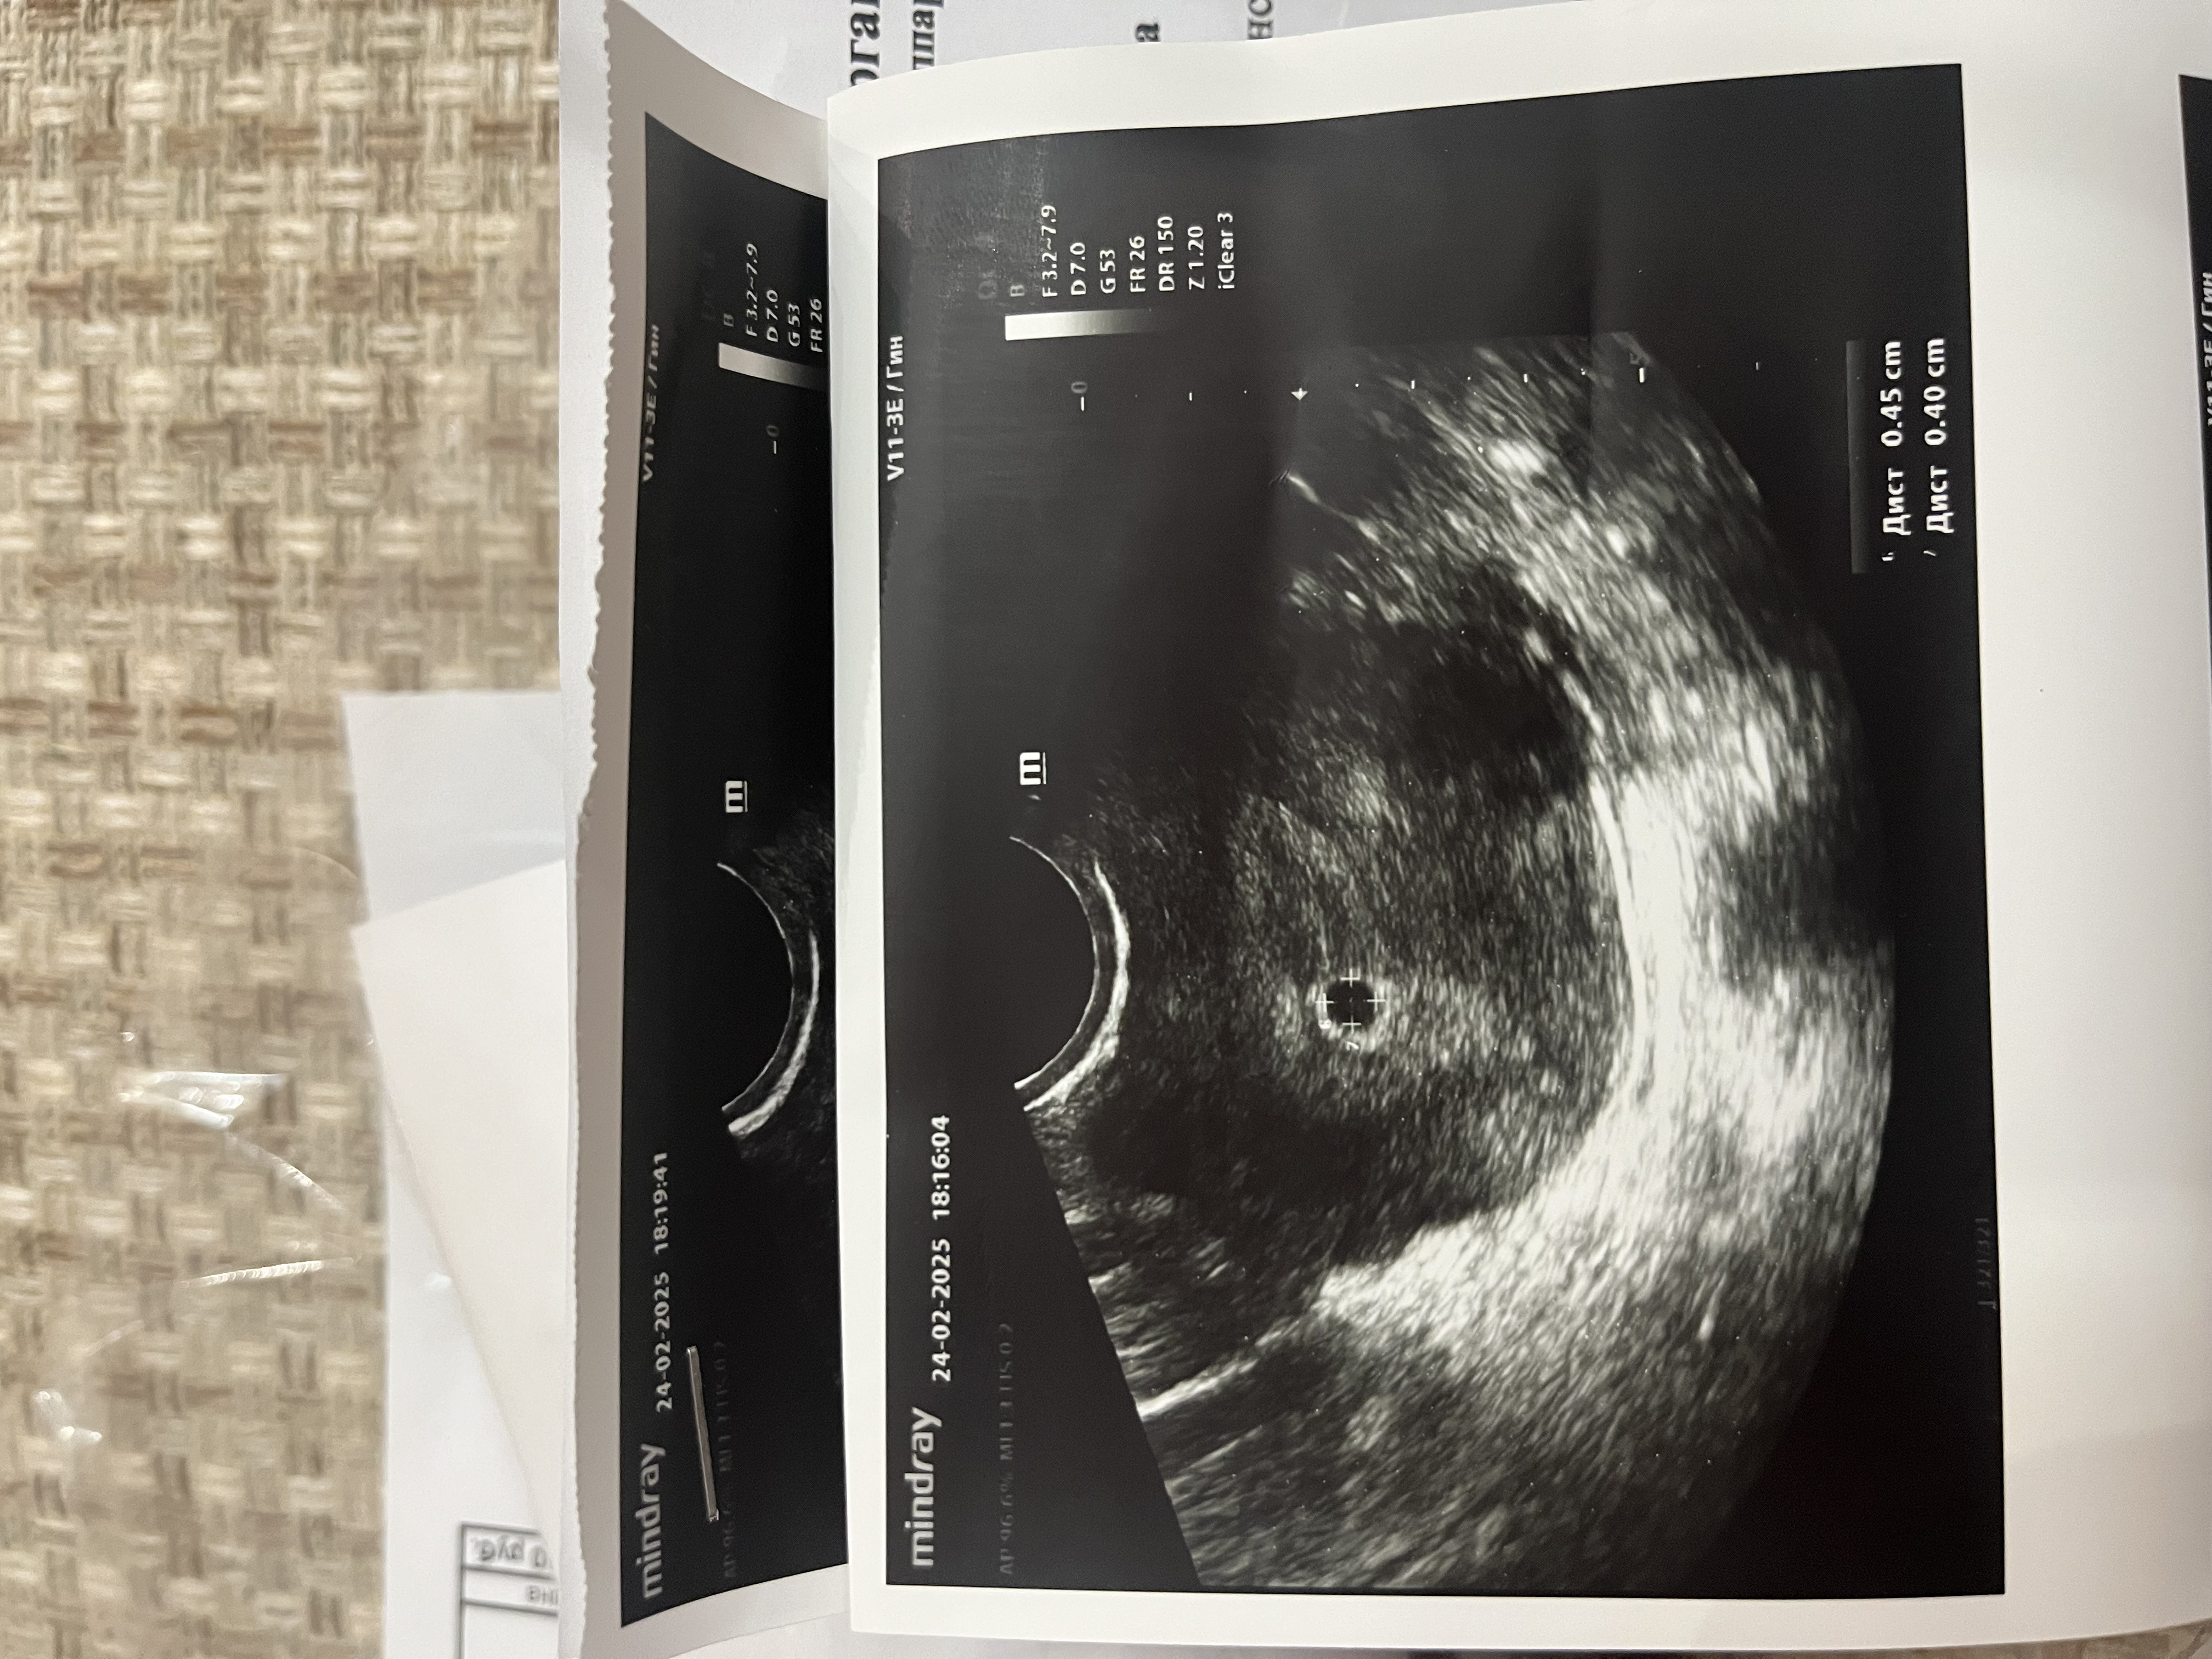

Все же Мальчик? 🤔 Что это на узи в правом углу? 6-7 нелеля

Оксана, сходила на узи, все хорошо) сердечко бьётся